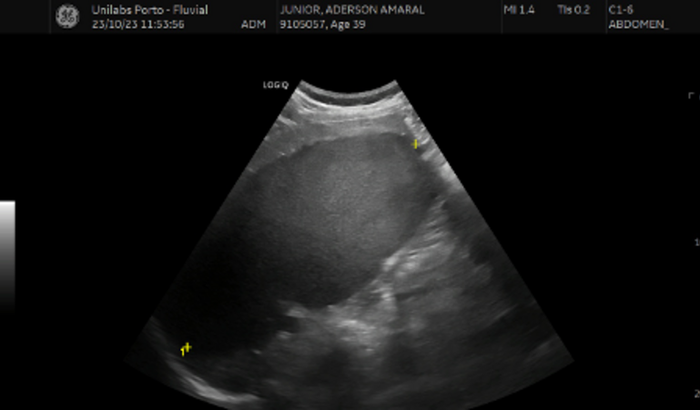

Eu sou Junior(Dedek0), vivo em Portugal há dois anos, vim realizar um sonho de mudança de vida e estou na luta disso, desde que cheguei, criei um canal no YouTube para mostrar minha rotina, que é o @umbrasileironoporto, no primeiro dia do mês de novembro desse ano eu estava voltando da academia e senti uma sensação de quase um desmaio, tontura, suando frio, calafrio, e desde esse dia não fiquei bem, essa mesma situação já tinha acontecido comigo em 2020, mas nunca descobri oque era porque após um tempo eu voltava ao normal, só que decidi investigar a fundo dessa vez, fiz muitos exames aqui em Portugal, pois não estava conseguindo trabalhar, devido a tontura, vista embaçada e mal estar, e quando cheguei na ecografia do abdômen, descobri um cisto de 20cm no baço, algo que nem passava por monja cabeça, já estou quase um mês sem trabalhar, e sem previsão de voltar, pois estou com a tontura e visão embaçada impossibilitando trabalhar, ja que trabalho como motorista de app aqui em Portugal, estou em outro país longe da família, gastei praticamente tudo que consegui juntar pra fazer os exames, agora estou parado sem trabalhar, sem ter como pagar nada, e sei que infelizmente o hospital público pode demorar muito aqui pra fazer outros exames que vão ser necessários antes da cirurgia, e essa vakinha é pra eu conseguir pagar tudo nesse período e tentar agilizar ao máximo alguns exames no particular, pois apesar de tudo e um cisto muito grande e que preciso retirar o mais rápido possível, sei que nao tenho condicoes de fazrr a cirurgia no particular, mas espero contar com ajuda da famlia, dos amigos, conhecidos e todas pessoas de bom coração que queira ajudar, tem sido uns dos piores dias da minha vida, nao estava preparado para isso e acho que ninguem nunca esta, mas gracas a deus e um cisto e nao nada pior, não tá sendo fácil, eu ainda estava tentando me organizar aqui e isso me deixou totalmente sem rumo, atrasou tudo e ainda destruiu meu psicológico, pois até sair o resultado só pensei o pior, vários dias tremendo sozinho, ansiedade a mil, venho pedir essa ajuda, pois sozinho não consigo, quero continuar com meu sonho e isso vai ajudar a vencer essa batalha, pois sei que vai ser uma, doe se seu coração quiser, e independente de tudo torçam por mim, ja me considero muito sortudo por ter sido um cisto(mesmo sendo algo nao tao simples tb)

*vou atualizando as imagens dos exames.